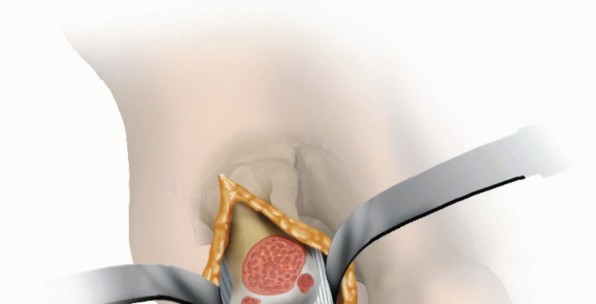

The joint capsule and the short flexors with the sesamoid bones are released subperiosteally using a McGlamry elevator (TECH FIG 3A,B).

The phalangeal attachment of the plantar capsule and the insertion of the short flexor muscles are released (TECH FIG 3C).

This maneuver must be performed cautiously so as not to detach the tendons from their insertion.

- TECH FIG 3 • A. Plantar release using a McGlamry elevator. B. Plantar release using a McGlamry elevator. C. Release of the distal capsule and short flexors using a scalpel. D. Plantarflexion after plantar release and resection of osteophytes.